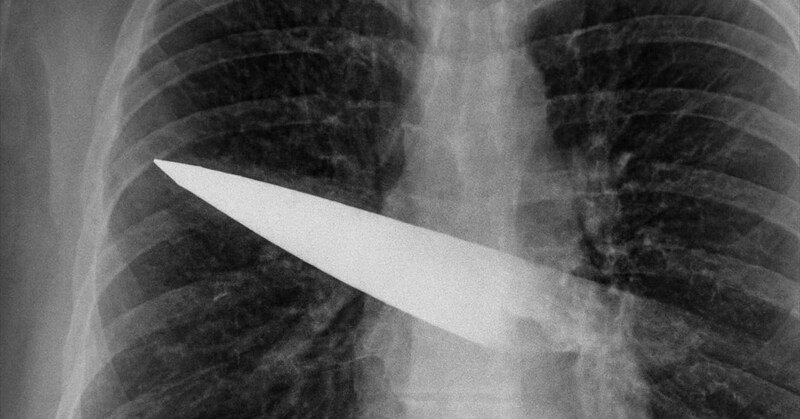

その後、病院でX線検査を受けて初めて、右胸の奥深くに金属製のナイフの刃が残っていることが判明したのです。

こちらは胸部にナイフが刺さっていることを示すX線画像。

さらにCTスキャンでは、刃は背中の第5・6肋骨の間から体内に入り、胸の前面(第3・4肋骨の間)まで貫通していることが分かりました。